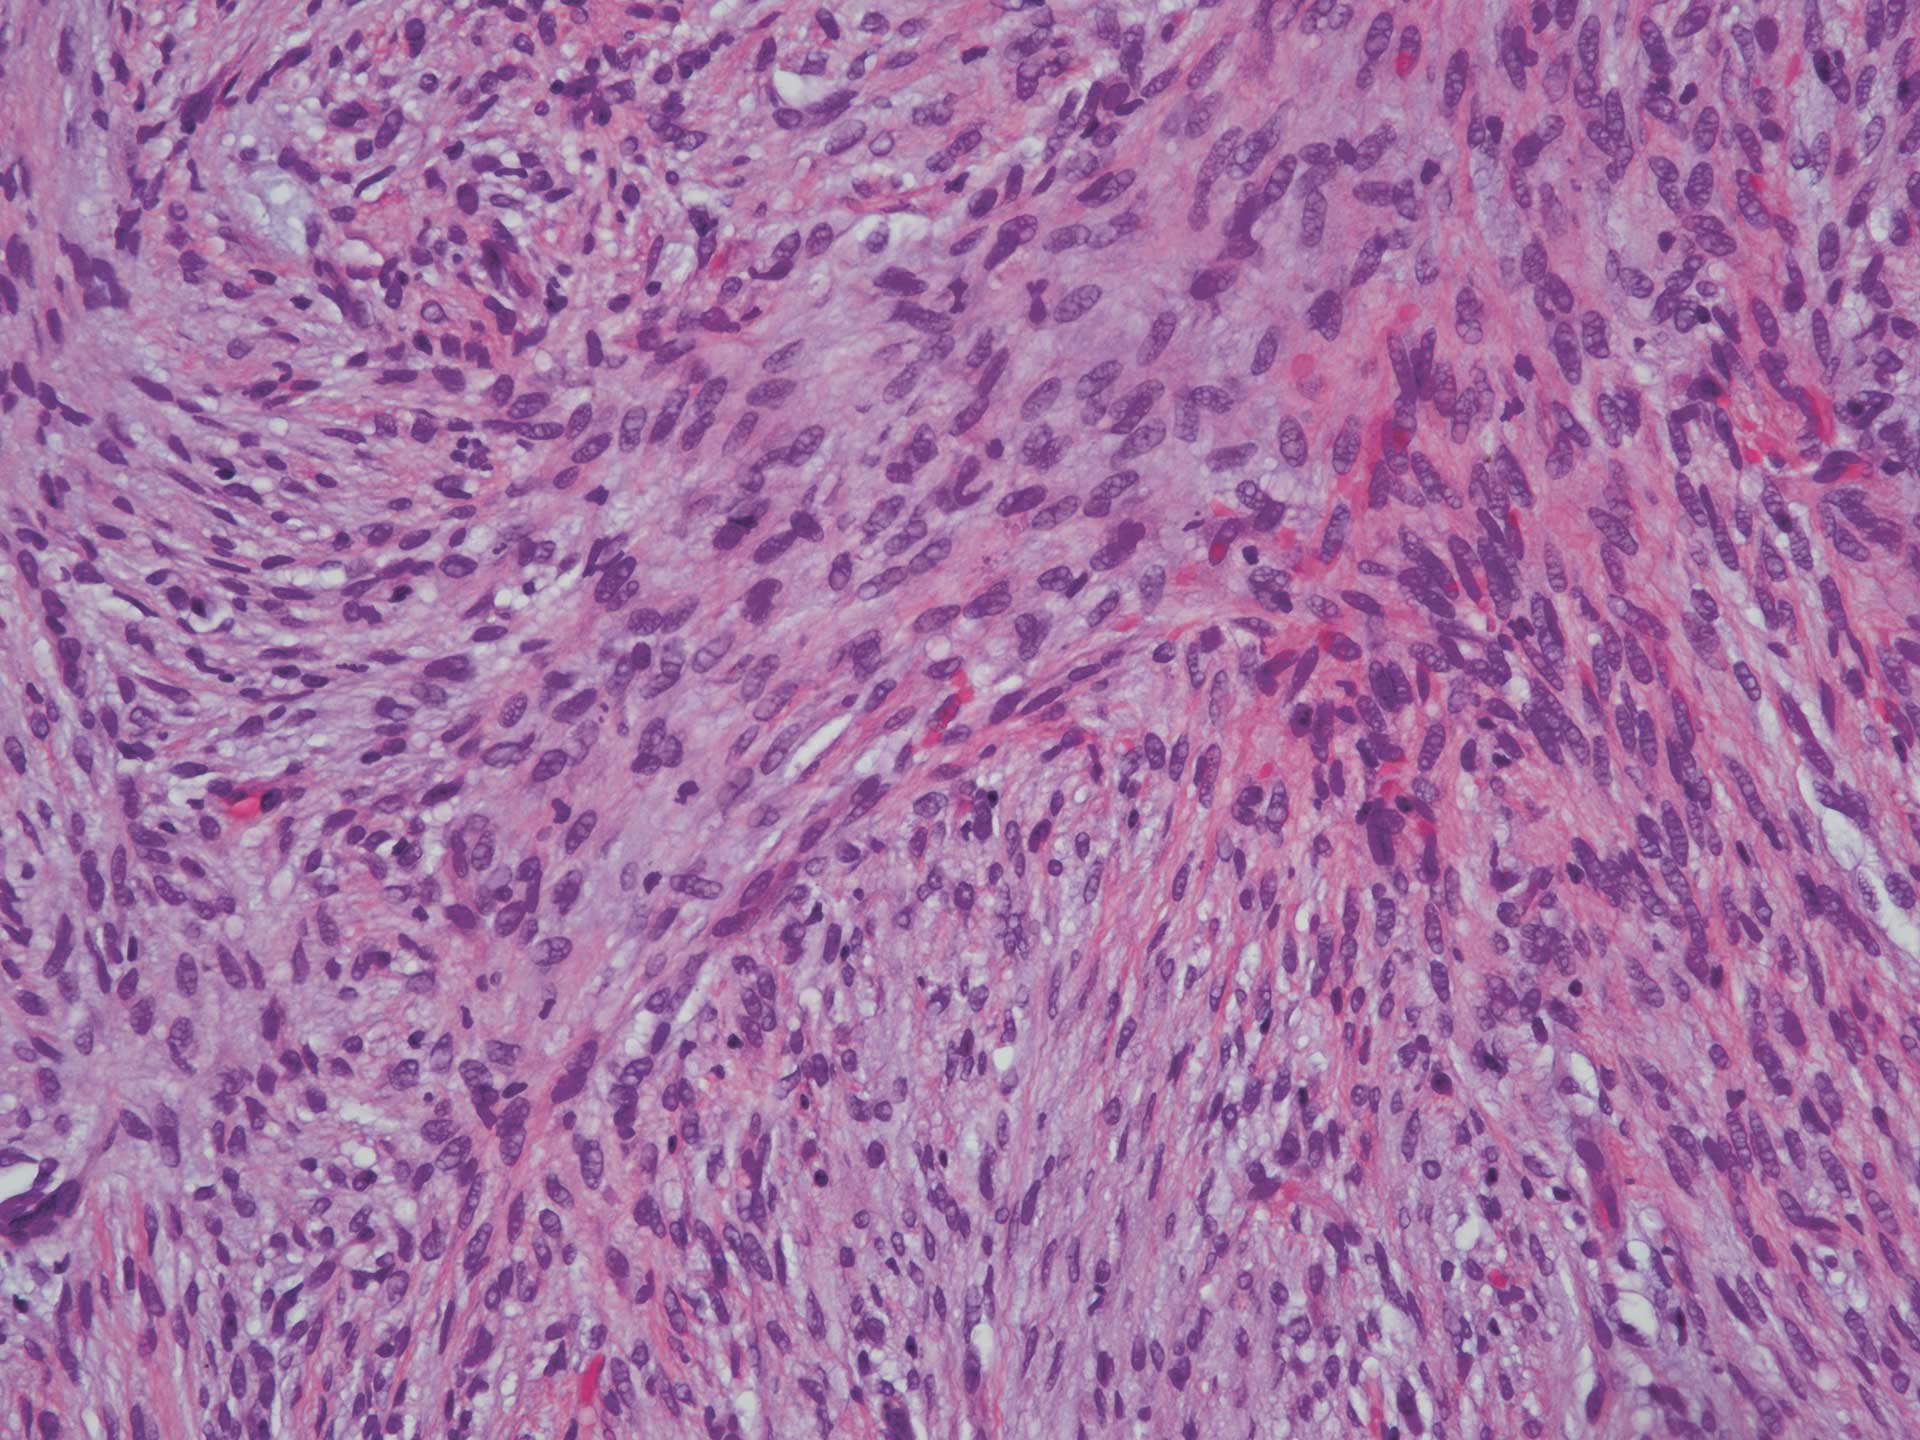

Mikroskopisk fant man i rutinefarget snitt (HE-snitt) et ikke-innkapslet fibrøst bindevev som var relativt cellerikt (figur 3). Fibroblastene var spolformet og dannet et stråmatte- eller fiskestimlignende mønster. De var regelmessige, uten pleomorfi, og det ble ikke sett økt antall mitoser (figur 4). Videre fant man et noe mer finfibret bindevev som inneholdt mange små blodkar. Det var kun et ubetydelig antall kroniske betennelsesceller i vevet. I vevets periferi var det litt nydannet beinvev omgitt av osteoblaster. Beinvevet ble antatt å være metaplastisk/reaktivt.

Figur 4 HE 20x objektiv. Spolformede fibroblaster arrangert i et stråmatteformet mønster med orientering i ulike retninger. Vi ser ingen påfallende pleomorfi eller mitoser og heller ingen påfallende forekomst av betennelsesceller.